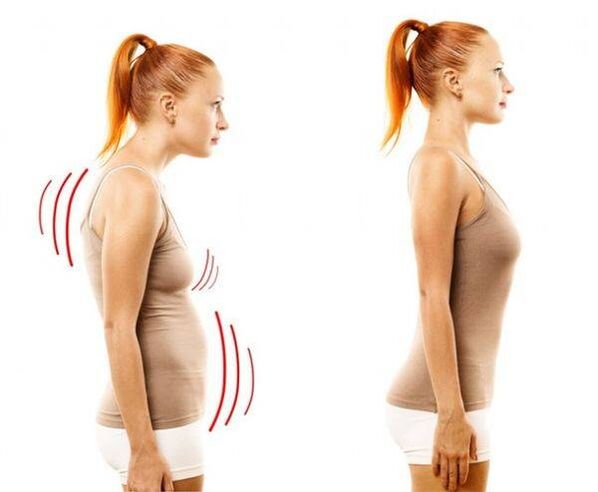

In this disease, the core of the spinal disc becomes thinner and dries out, the fibrous tissue around it begins to deteriorate, and the cartilage tissue undergoes negative changes.The spine becomes able to cope with normal loads - and this is mainly expressed in the appearance of pain, which is vaguely expressed at first, but becomes more and more intense over time.However, with significant stress - sedentary lifestyle, sedentary work, constant stress, bad posture and back injuries - sooner or later osteochondrosis affects the chest region.The disease is considered very common - every third adult suffers from it.

Osteochondrosis of the spine is expressed in scoliosis;sometimes the disease spreads to the cervical vertebrae and causes loss of voice.

Almost all of the listed methods are not aimed at eliminating osteochondrosis as such, but at relieving inflammation and reducing the intensity of pain.The main goal of treatment for breast osteochondrosis is to eliminate pain.At the same time, manual therapy and exercise therapy can "straighten" the spine, increasing the distance between the vertebrae and preventing compression.However, it is the duty of the patient to perform therapeutic exercises regularly - otherwise it will not give any result.